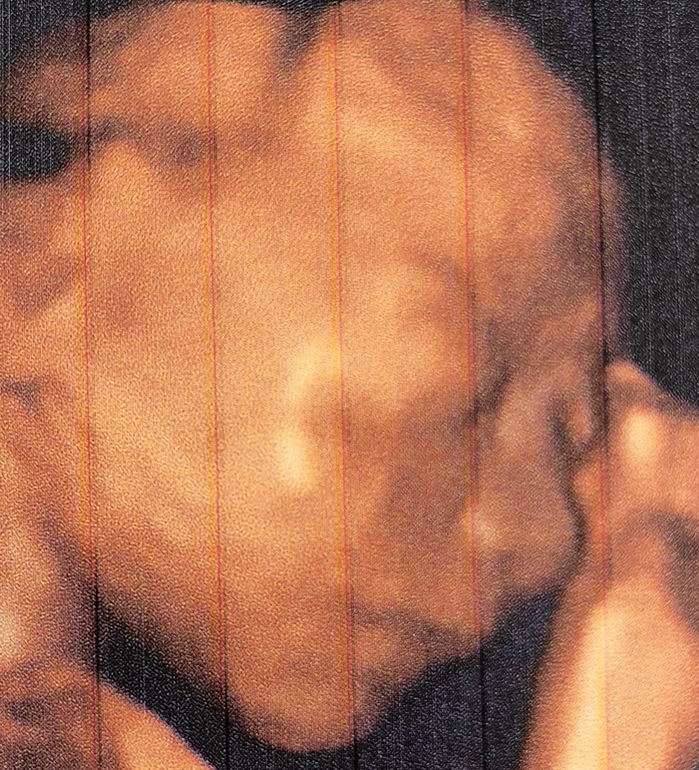

20+6 недель

Красотулька моя, носик (чуть вздёрнут) и губки будто мои 🙈.

Очень долго не давала нормально просмотреть сердце, крутилась, шевелилась. Есть фотка где нога вообще у головы 😅. Весим ~500 грамм, по развитию опережаем на 1 неделю. Все хорошо, все органы в порядке.

Ага 😍. Иногда смотрю на это фото и умиляюсь. На третьем узи не смогли нормально сфотографировать. Узист мне показала лицо в 3Д, там получалось размазанное фото, щеки как у хомяка, и будто недовольная была.